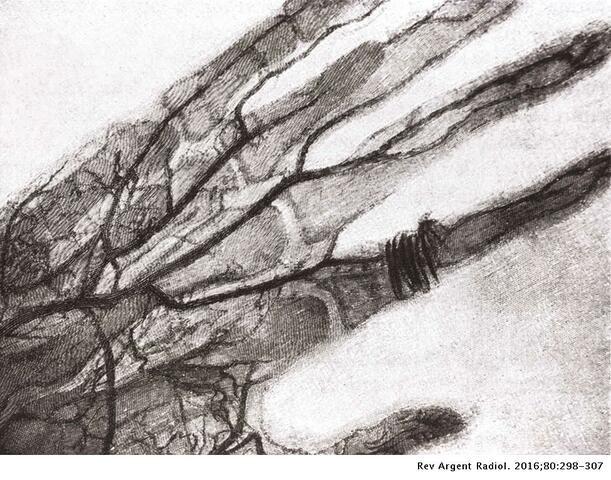

Primera radiografía de la mano de su esposa.